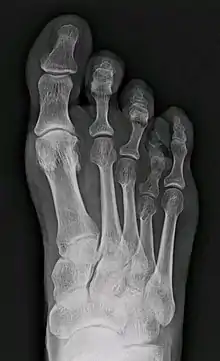

Braquimetatarsia (del griego brachys, corto, y metatarsia, relativo al metatarso) o metatarso hipoplásico es una condición médica en la cual existe uno o más metatarsos anormalmente cortos.[1] El tipo más común de braquimetatarsia es la que afecta al primer metatarsiano. Esta es conocida como Pie de Morton

Esta enfermedad puede deberse a un defecto congénito o puede ser adquirida.[1] Generalmente afecta al cuarto metatarso y está presente en ambos pies (braquimetatarsia bilateral). En caso de que el defecto esté presente en más de un dedo se le denomina braquimetapodia.[5] En caso de que el metatarso afectado sea el primero, esta malformación se conoce como síndrome de Morton. Frecuentemente, genera un inconveniente desde el punto de vista estético e incluso causa otros problemas como metatarsalgia, callosidades o dificultad para calzarse. Existen varios procedimientos médicos para tratar esta condición.[1]